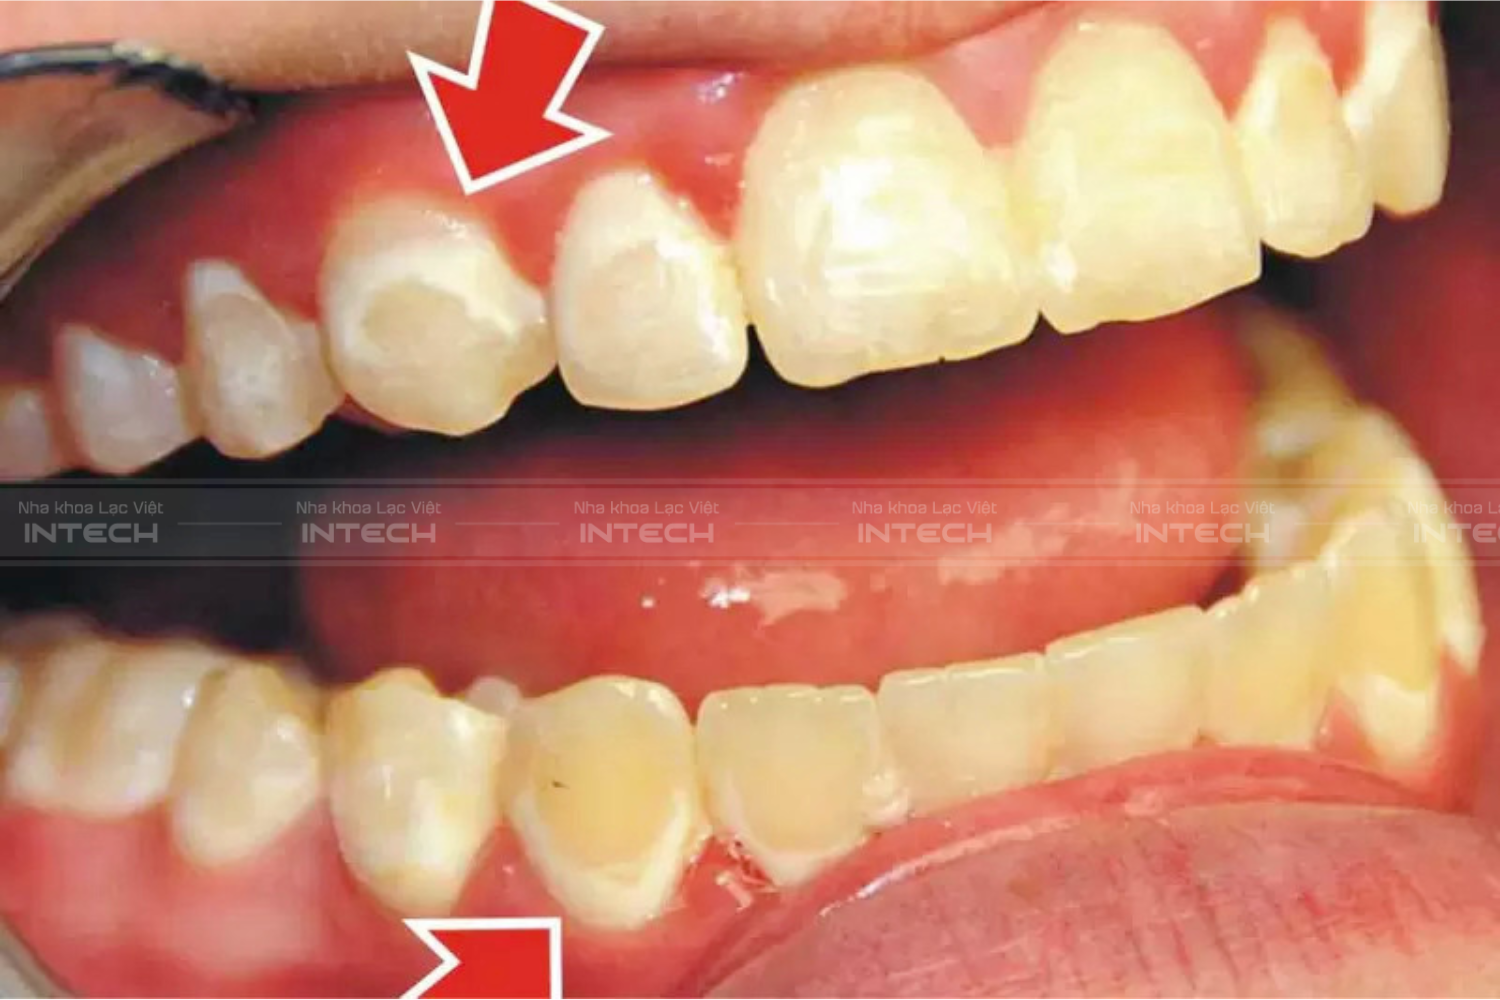

2. Huỷ khoáng men răng

Đây là tác hại của niềng răng thứ hai mà bác sĩ nghĩ nó khá là phổ biến đấy. Đây được gọi là huỷ khoáng men răng. Nguyên nhân gây nên tình trạng này cũng là do vệ sinh răng miệng kém kèm với việc sử dụng quá nhiều món chứa đường hoặc có tính axit cao trong bữa ăn. Theo thời gian, vi khuẩn tấn công mạnh mẽ khiến cho men răng bị mài mòn. Kéo theo đó lượng khoáng chất canxi của răng bị hao hụt thậm chí mất đi.

Các bạn có thể nhận thấy biểu hiện của nó khá rõ rệt thông qua hình ảnh này, các đốm trắng liti xuất hiện trên thân răng, nếu người niềng không điều trị kịp thời, rất có thể những vết trắng này sẽ loang dần ra, rất mất thẩm mỹ. Nguy hiểm hơn, nếu huỷ khoáng men răng lâu ngày có thể gây nên hậu quả gãy vỡ, sứt mẻ và nặng nề nhất là rụng răng.

Khi bị bệnh nhân gặp tình trạng này, thường bác sĩ sẽ điều trị bằng phương pháp ICON DMJ, điều trị dựa trên nguyên lý thẩm thấu rất đơn giản. Sau khi etching bằng Icon-Etch, chất thẩm thấu là nhựa resin không hạt độn, có tính chảy lỏng cao, được bôi vào vùng răng bị đốm trắng. Nguyên lý mao dẫn đưa chất này thẩm thấu sâu vào trong men xốp, giúp khóa chặt các tổn thương sâu răng chưa tạo hốc.